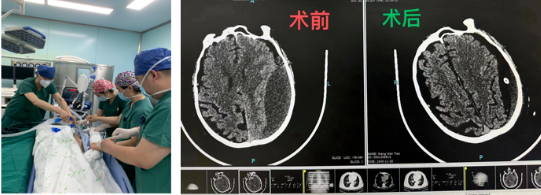

“健康所系,性命相托”是他们铭记在心的誓言。有一位82岁男性患者,同时患有多种慢性病,既往做过脑部手术和心脏搭桥手术,送来时已经呈昏睡状态,言语含糊不清,查体基本都无法配合,需进行立体定向颅内血肿钻孔引流术。麻醉科主任、手术室护士长紧急调配,手术室医护迅速到岗,加班加点配合手术治疗。术后第二天,患者转归良好。